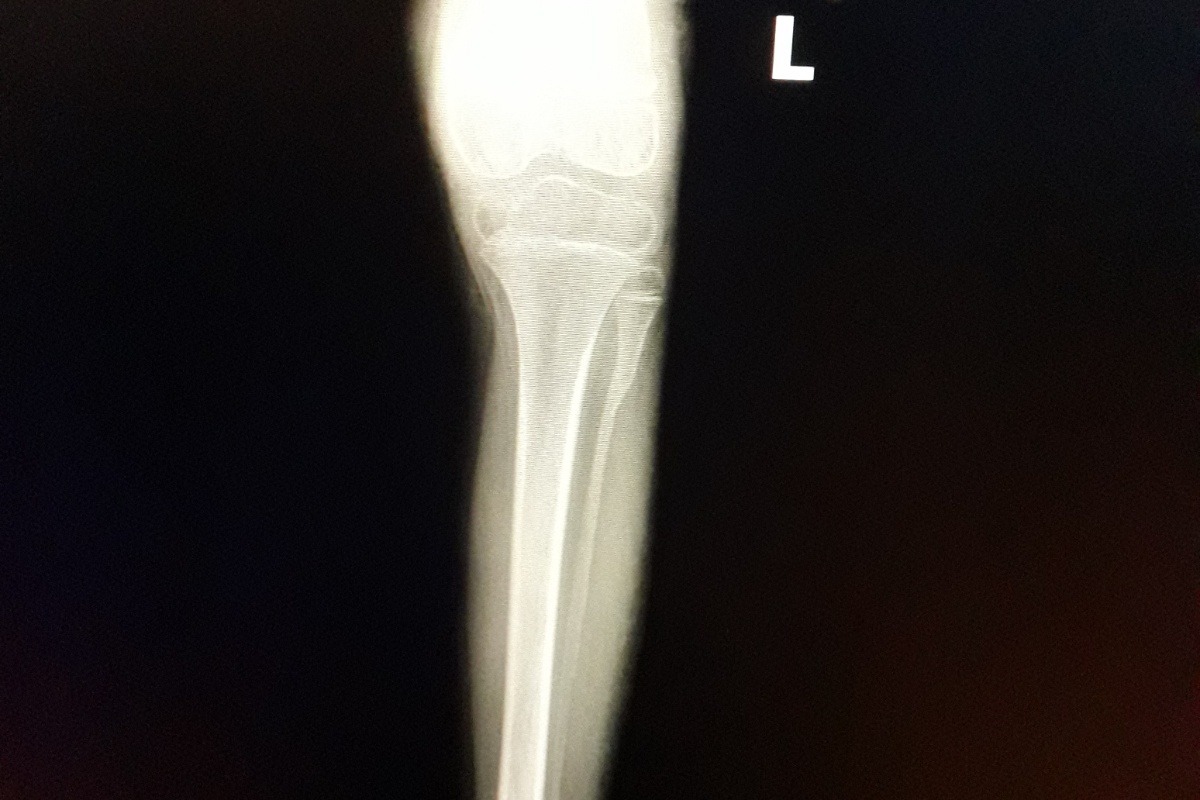

Ella es Camila Valentina, hace 4 meses sufrió una pequeña caída que causó una fractura de fémur en su pierna izquierda y a raíz de esto, a través de una placa y resonancia descubrieron un quiste fibroso en el fémur de la pierna izquierda que causó el debilitamiento del hueso.

Camila Valentina fue sometida a una doble cirugía hace 2 meses, una primera cirugía para extraer el quiste de su pierna izquierda y una segunda para extraer su peroné y ser usado como injerto óseo natural y así poder corregir el debilitamiento del fémur de su pierna izquierda.

She is Camila Valentina, 4 months ago she suffered a small fall that caused a fracture of the femur in her left leg and as a result of this, through a plaque and resonance they discovered a fibrous cyst in the femur of the left leg that caused the weakening of the bone.

Camila Valentina underwent double surgery 2 months ago, a first surgery to remove the cyst of her left leg and a second to remove her fibula and be used as a natural bone graft to correct the weakening of the femur of her left leg.

Injerto Óseo Fémur Pierna Izquierda:

Ausencia De Peroné Pierna Izquierda: